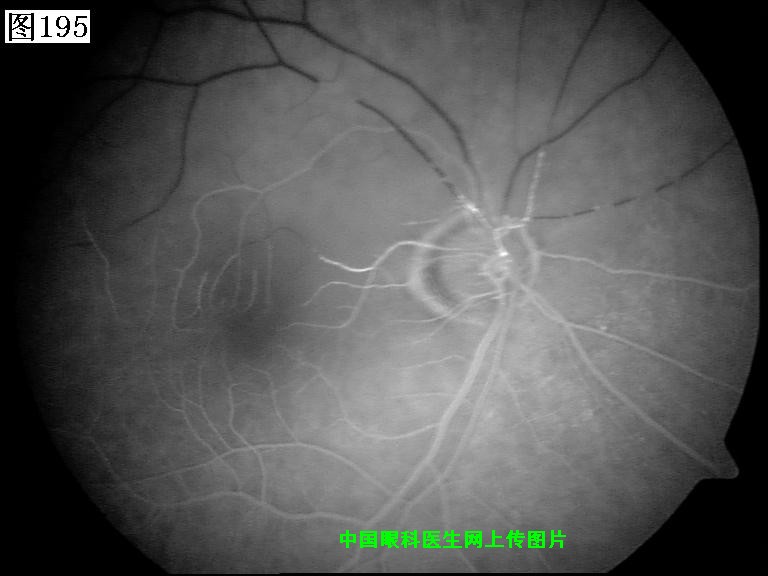

193 194 195 196